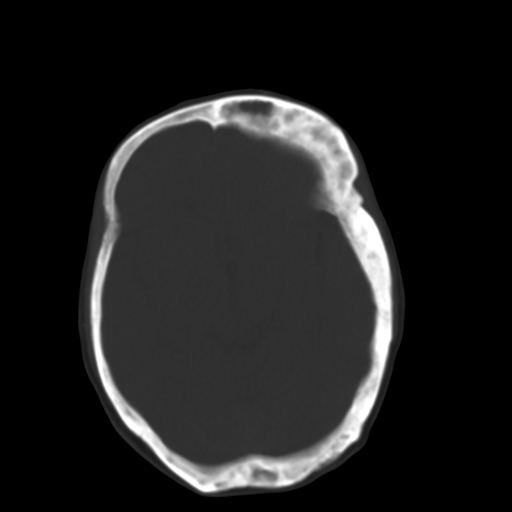

标题: CT17003:F58Y,骨纤维异常增殖征 [打印本页]

标题: CT17003:F58Y,骨纤维异常增殖征

女58y 头晕就诊

左侧额骨增厚,板障层密度增高。 支持骨纤维异常增殖症  。

符合颅骨骨纤维异常增殖症表现。